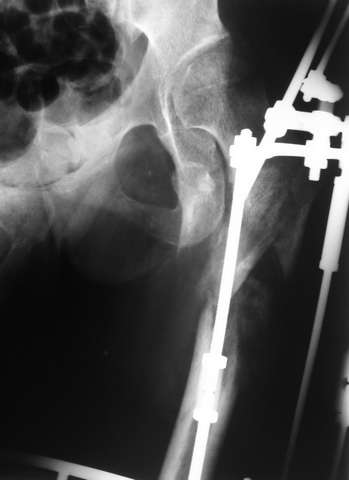

Мы закончили репозицию отломков бедренной кости в аппарате (рис. 1, 2) у нашей пациентки и на прошлой неделе сделали ей вторую операцию. Штифт удалось ввести закрыто. Верхний шеечный винт держался очень плохо, поэтому мы его убрали и решили не ставить. Нижний держал очень плотно. Рентгенограммы после операции прилагаю (рис. 3,4). Пока не получилось сделать нормальный аксиальный снимок (больная с трудом сгибает и отводит ногу в тазобедренном суставе). Пока сделали боковую проекцию в положении на здоровом боку со сгибанием здоровой ноги.